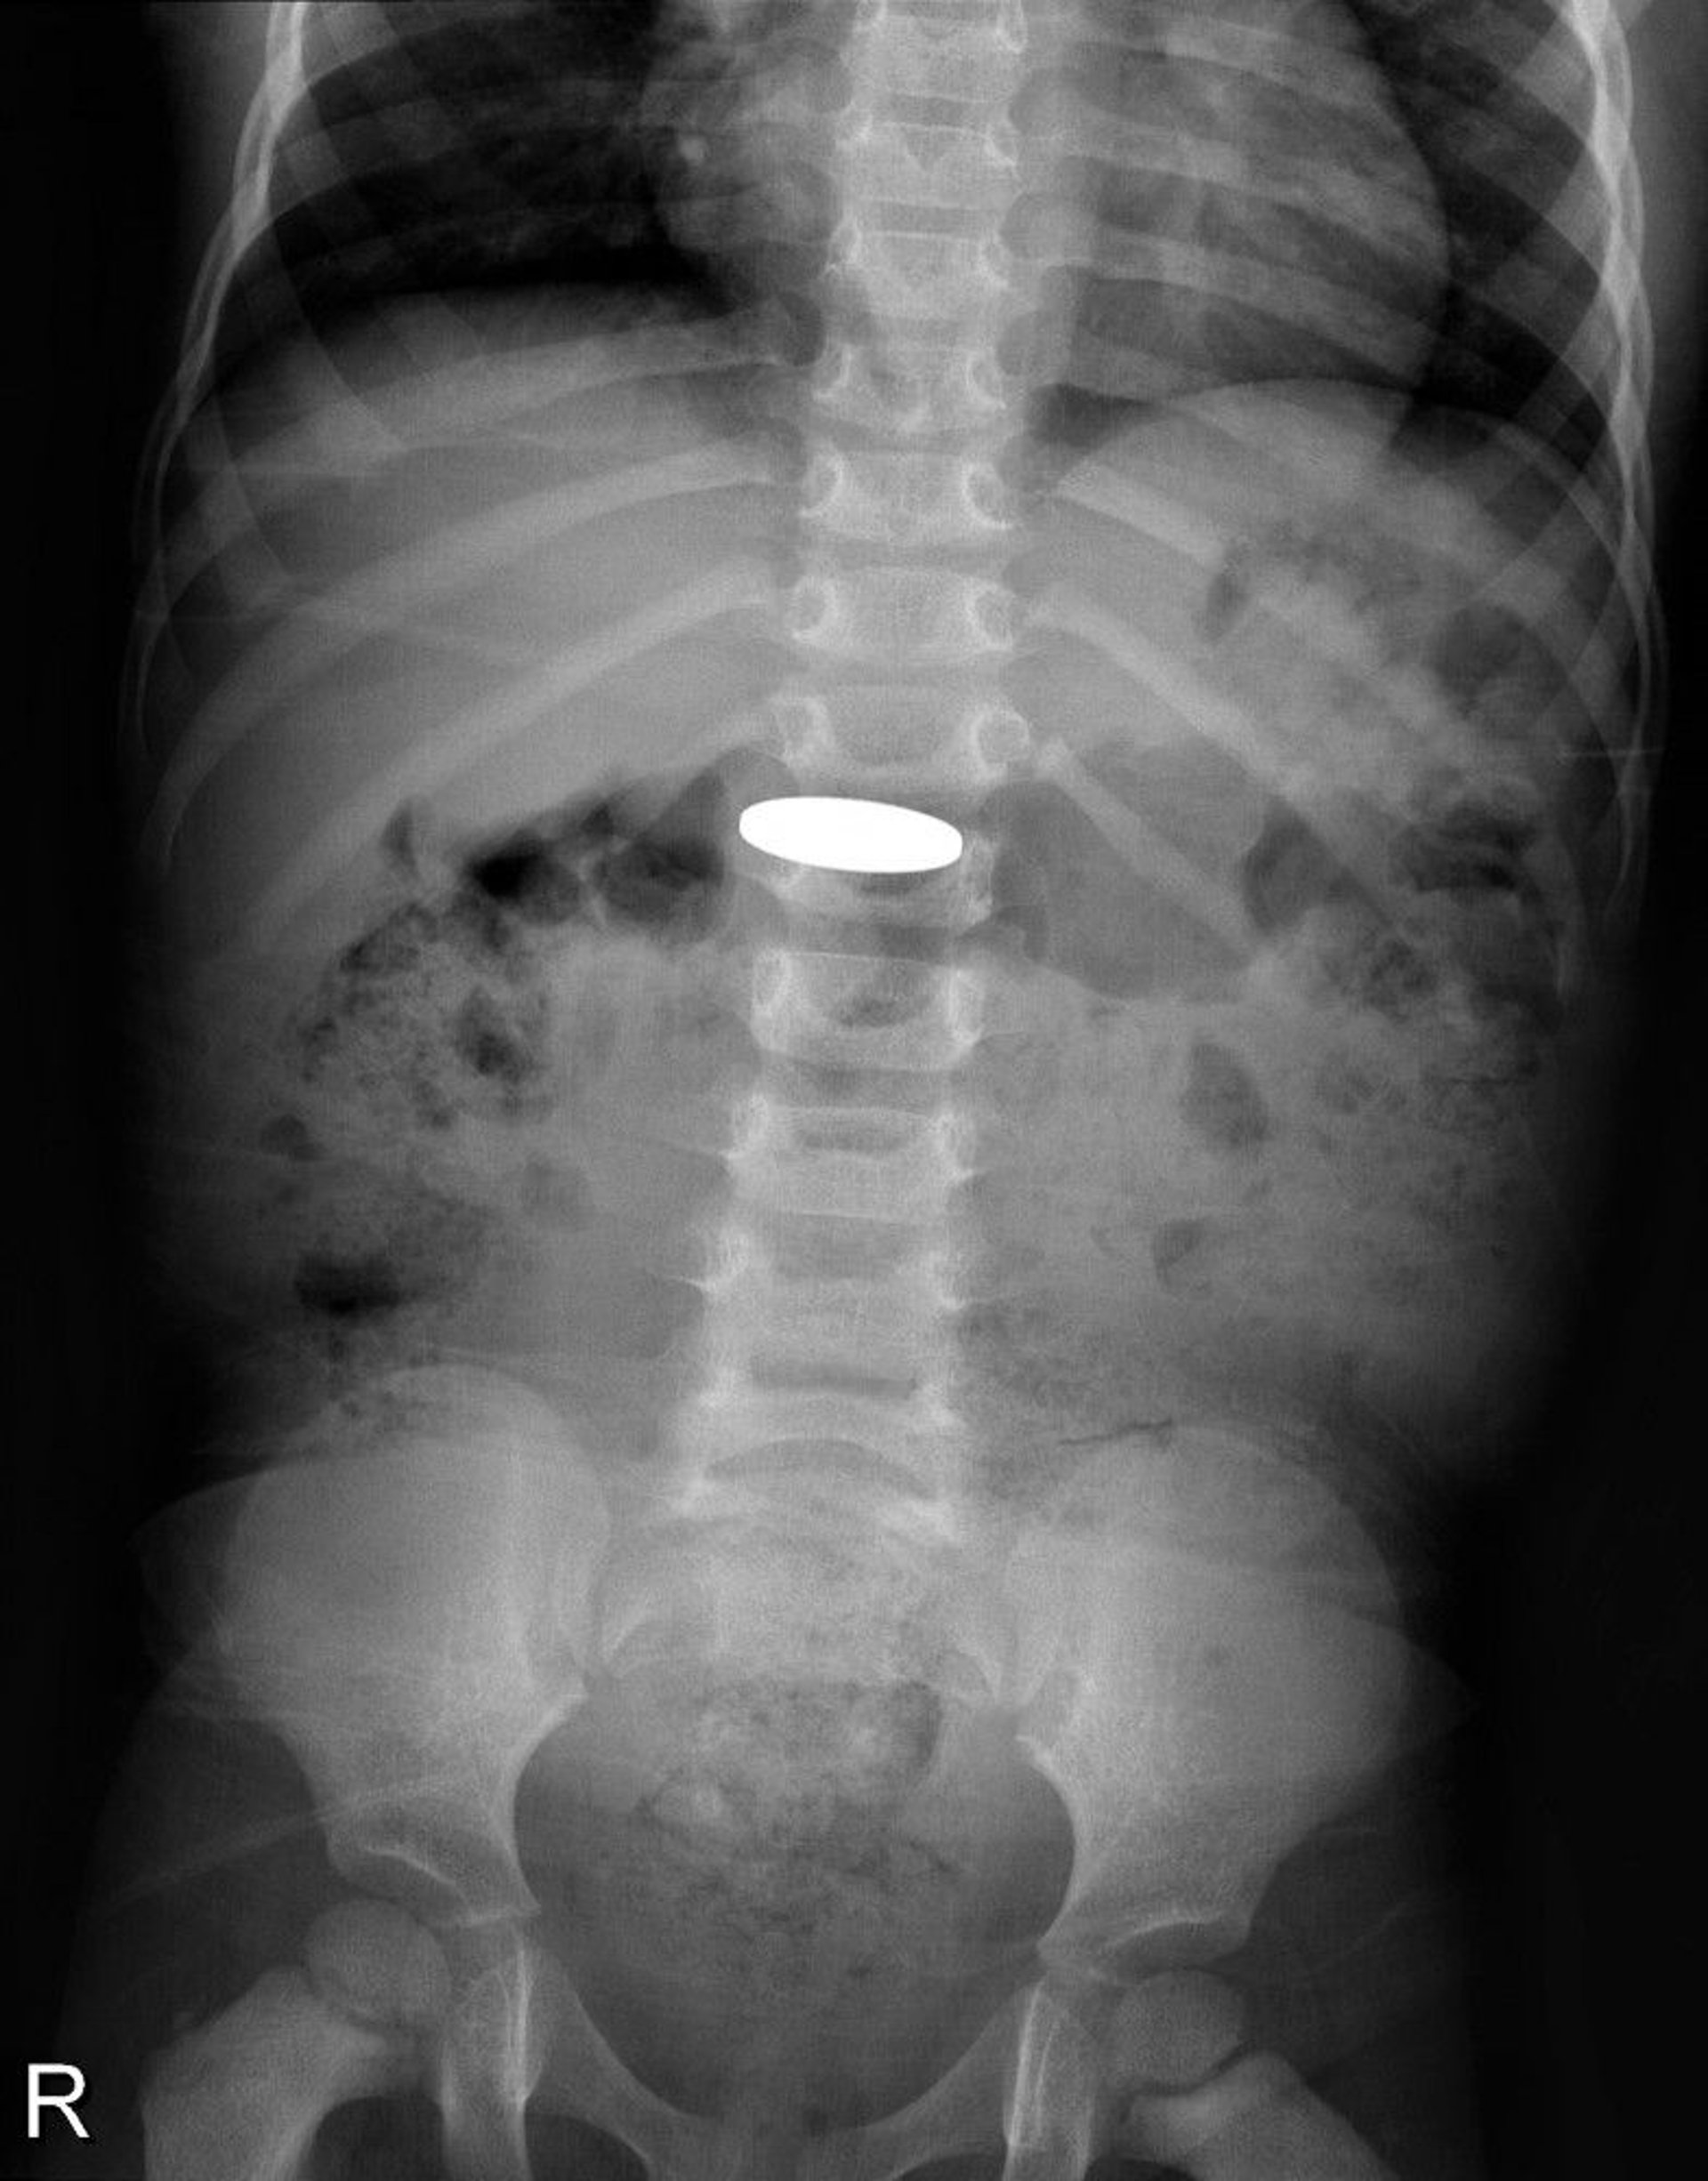

Foreign Body in the Digestive Tract (X-Ray)

This x-ray shows a coin that was swallowed by a young child.

DU CANE MEDICAL IMAGING LTD/SCIENCE PHOTO LIBRARY